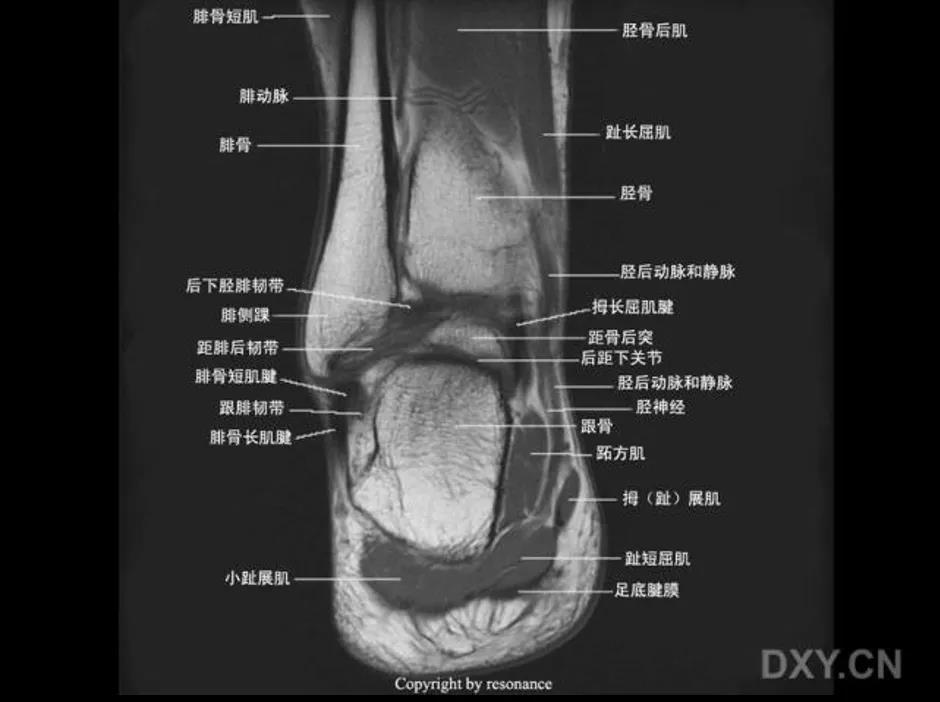

MRI:

三角韧带撕裂